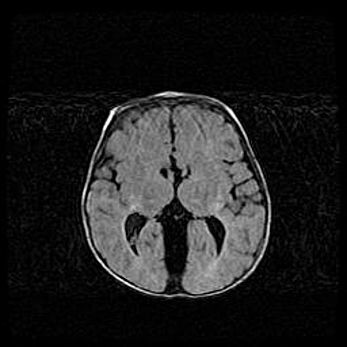

Открытая гидроцефалия.

Возраст: 9 месяцев 12 дней

Вес: 6800 г

Пол: мужской

Окружность головы: 41,5 см

Срок гестации: 28 недель

Гидроцефалия головного мозга у новорожденных имеет характерный признак: опережающий рост окружности головы приводит к визуально хорошо определяемой гидроцефальной форме сильно увеличенного в объёме черепа. Детские неврологи определяют следующие симптомы гидроцефалии у грудничков: выбухающий напряжённый родничок, частое запрокидывание головы, смещение глазных яблок к низу.